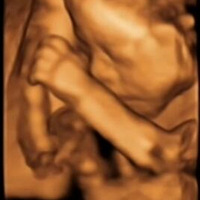

猴崽子,麻麻跟你约好9月见咯~

15524739 2016-05-21 20:01

4024 浏览 查看原帖